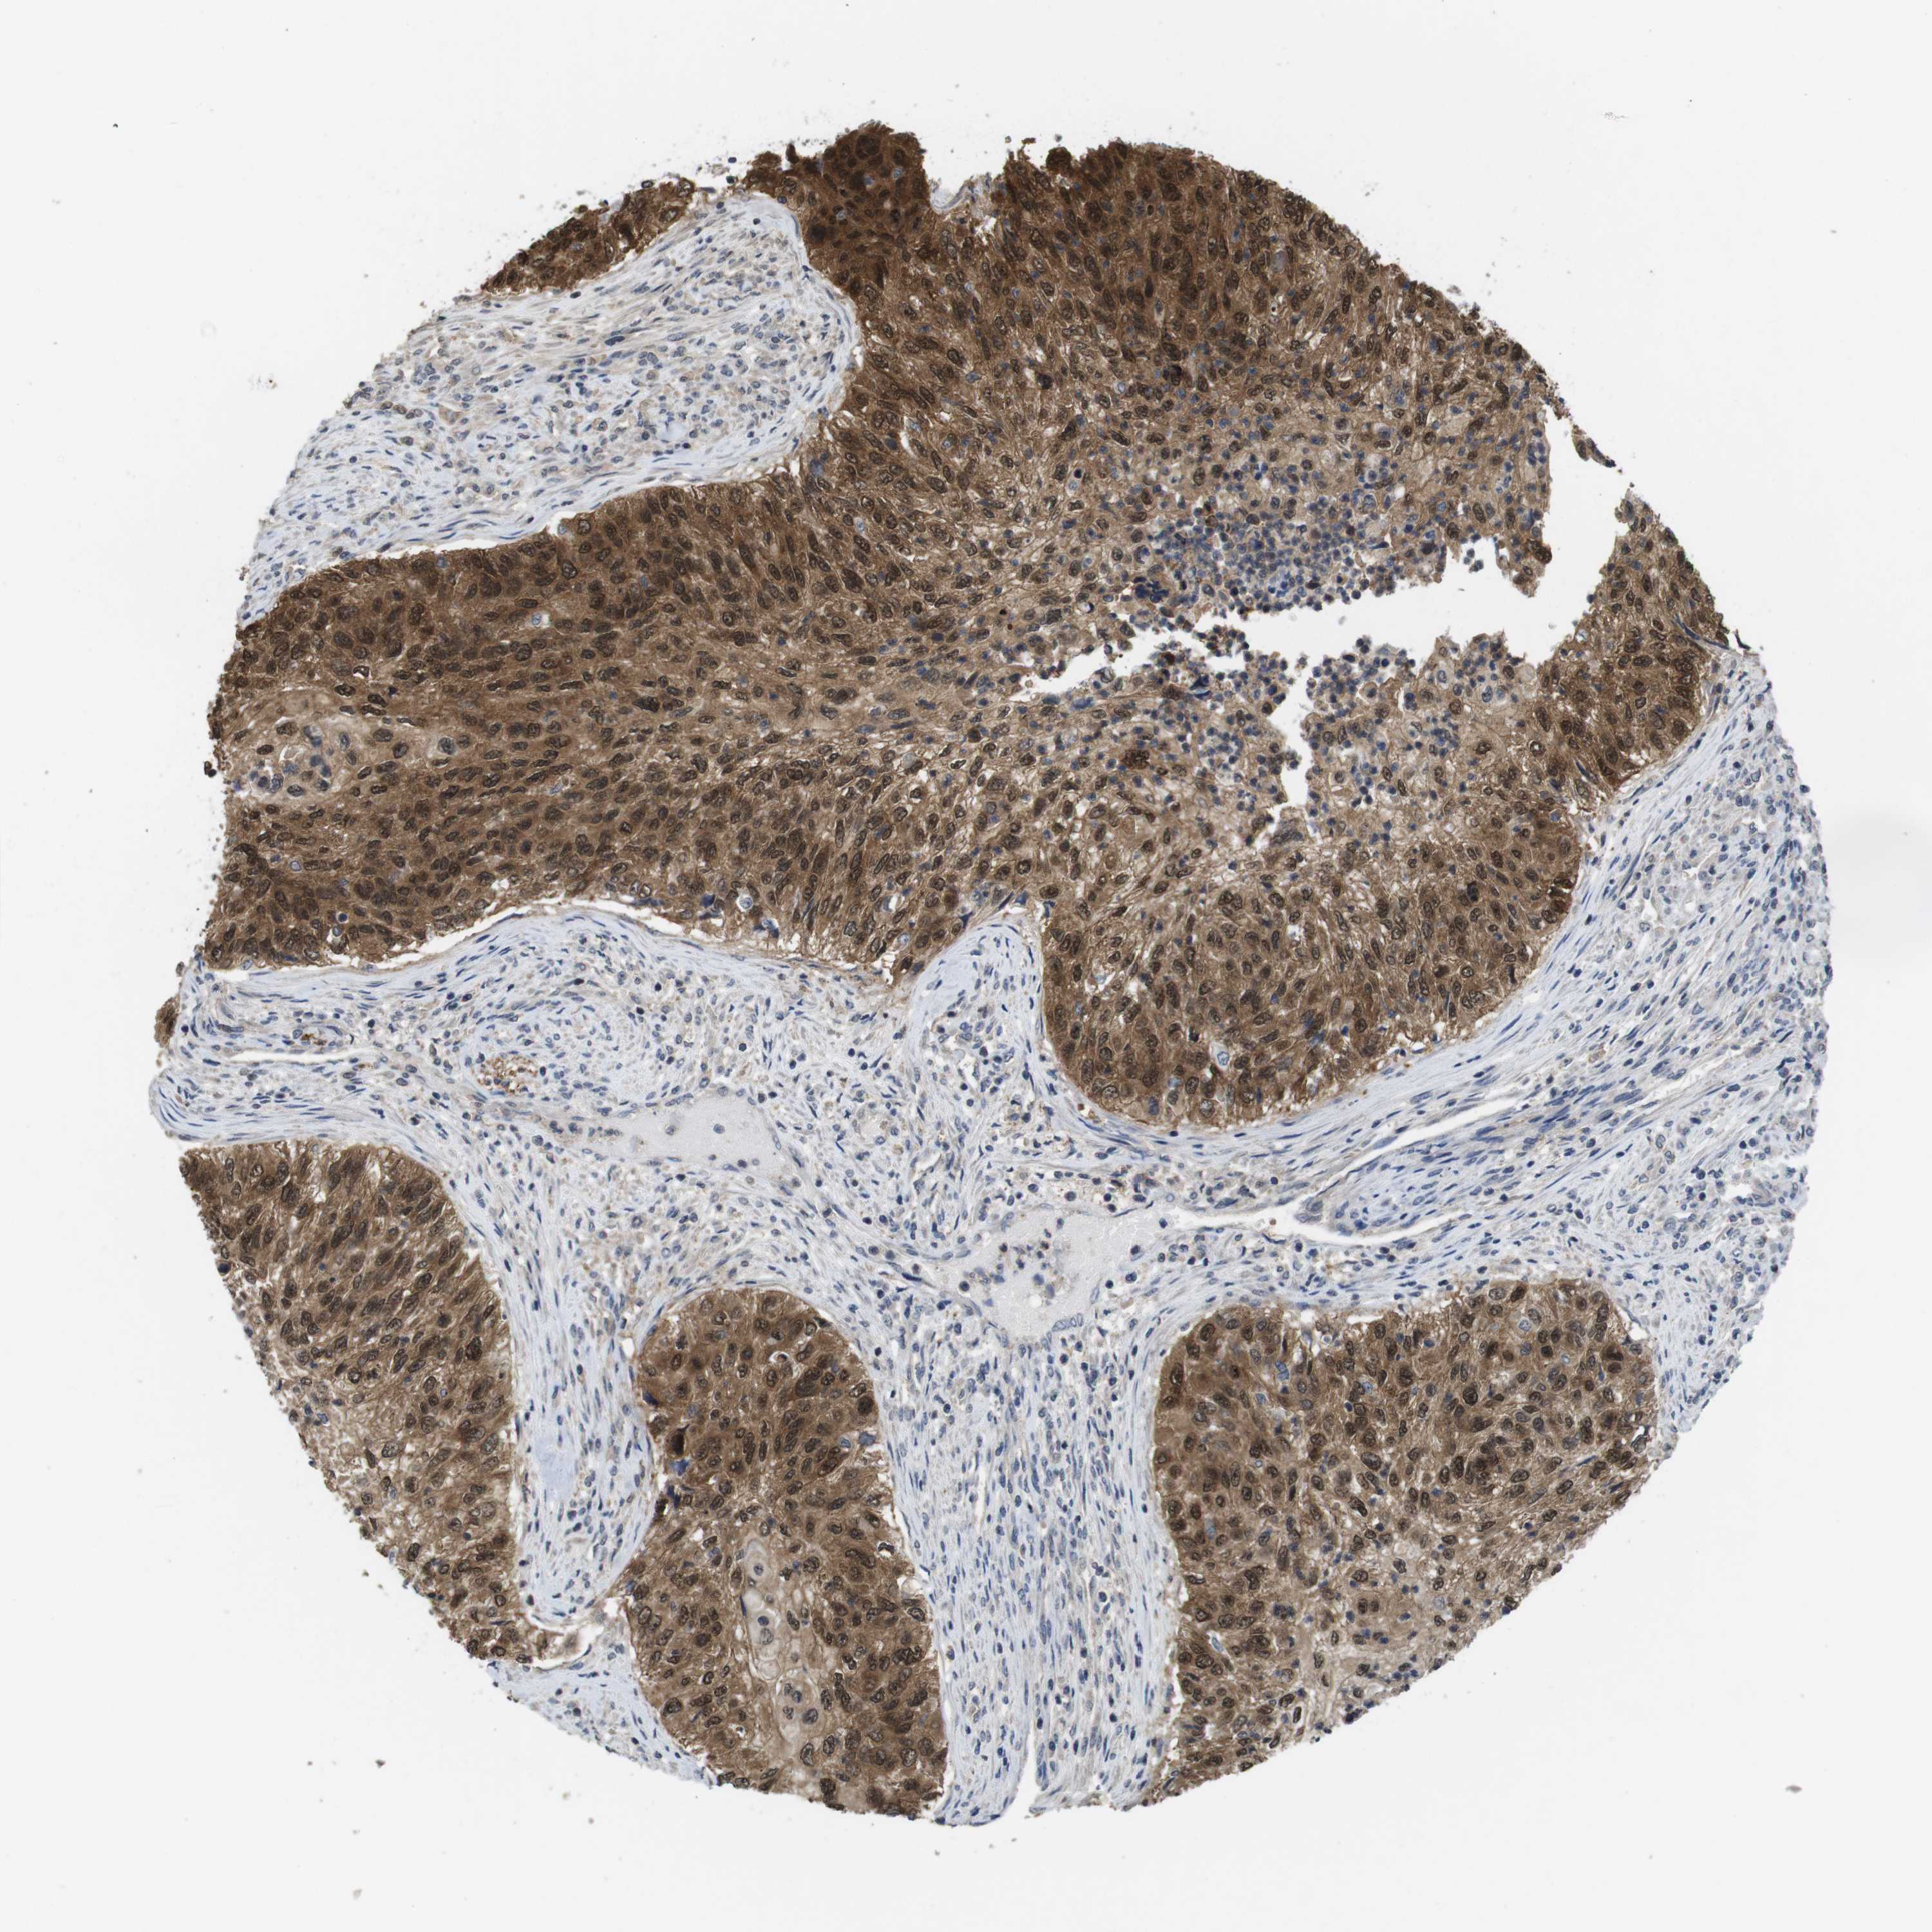

UROTHELIAL CANCER - Protein expressioni

A mouse-over function shows sample information and annotation data. Click on an image to view it in a full screen mode. Samples can be filtered based on level of antibody staining by selecting one or several of the following categories: high, medium, low and not detected. The assay and annotation is described here.

Note that samples used for immunohistochemistry by the Human Protein Atlas do not correspond to samples in the TCGA dataset.

Antibody stainingi

Antibody staining in the annotated cell types in the current human tissue is reported as not detected, low, medium, or high, based on conventional immunohistochemistry profiling in selected tissues. This score is based on the combination of the staining intensity and fraction of stained cells.

Each image is clickable and will lead to virtual microscopy that enables deeper exploration of all samples and also displays staining intensity scores, fraction scores and subcellular localization as well as patient and tissue information for each sample.

Antibody HPA001464

Antibody CAB010209

Urothelial carcinoma, High grade